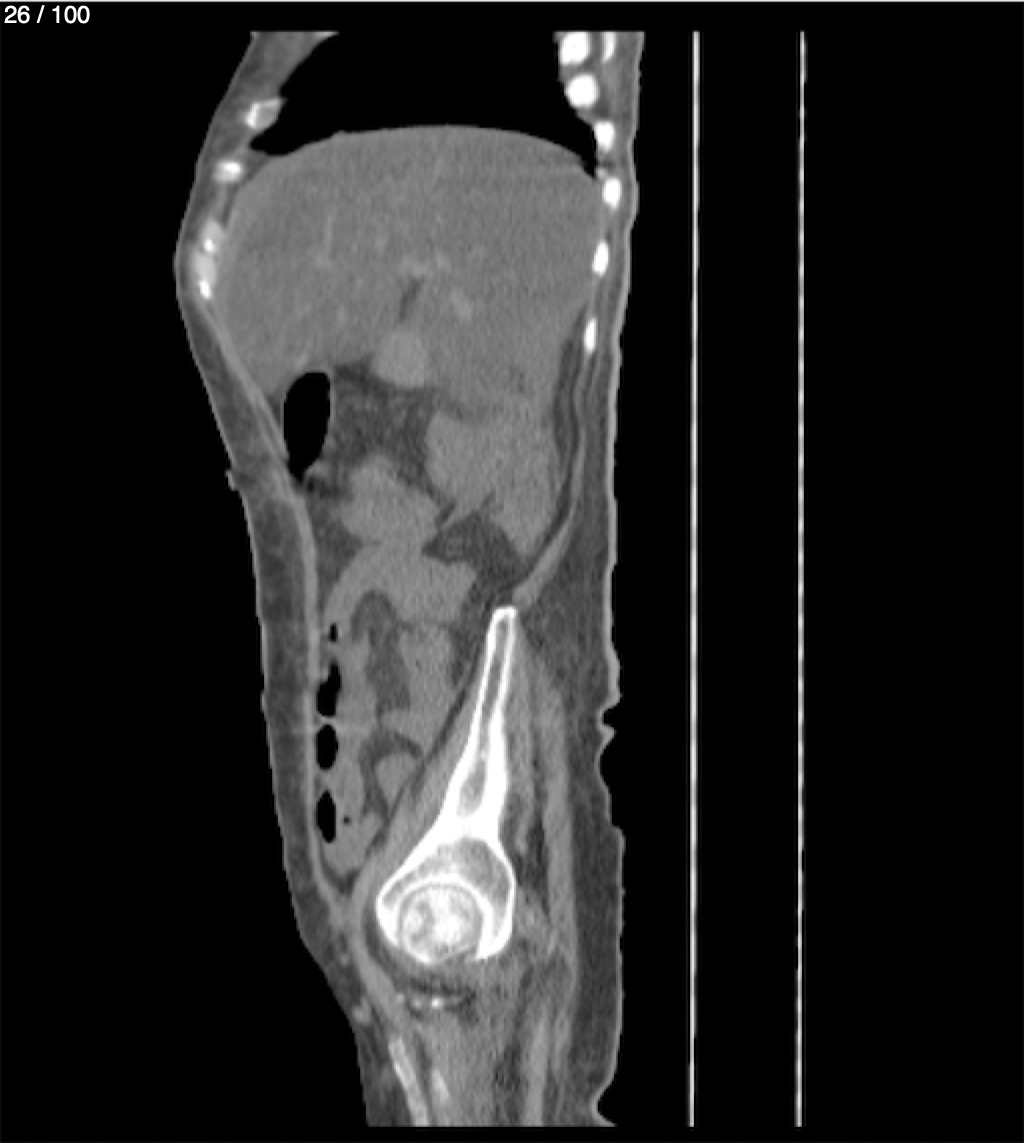

Hilda Geronimo Mendez 60A - T.C Abdomen Simple